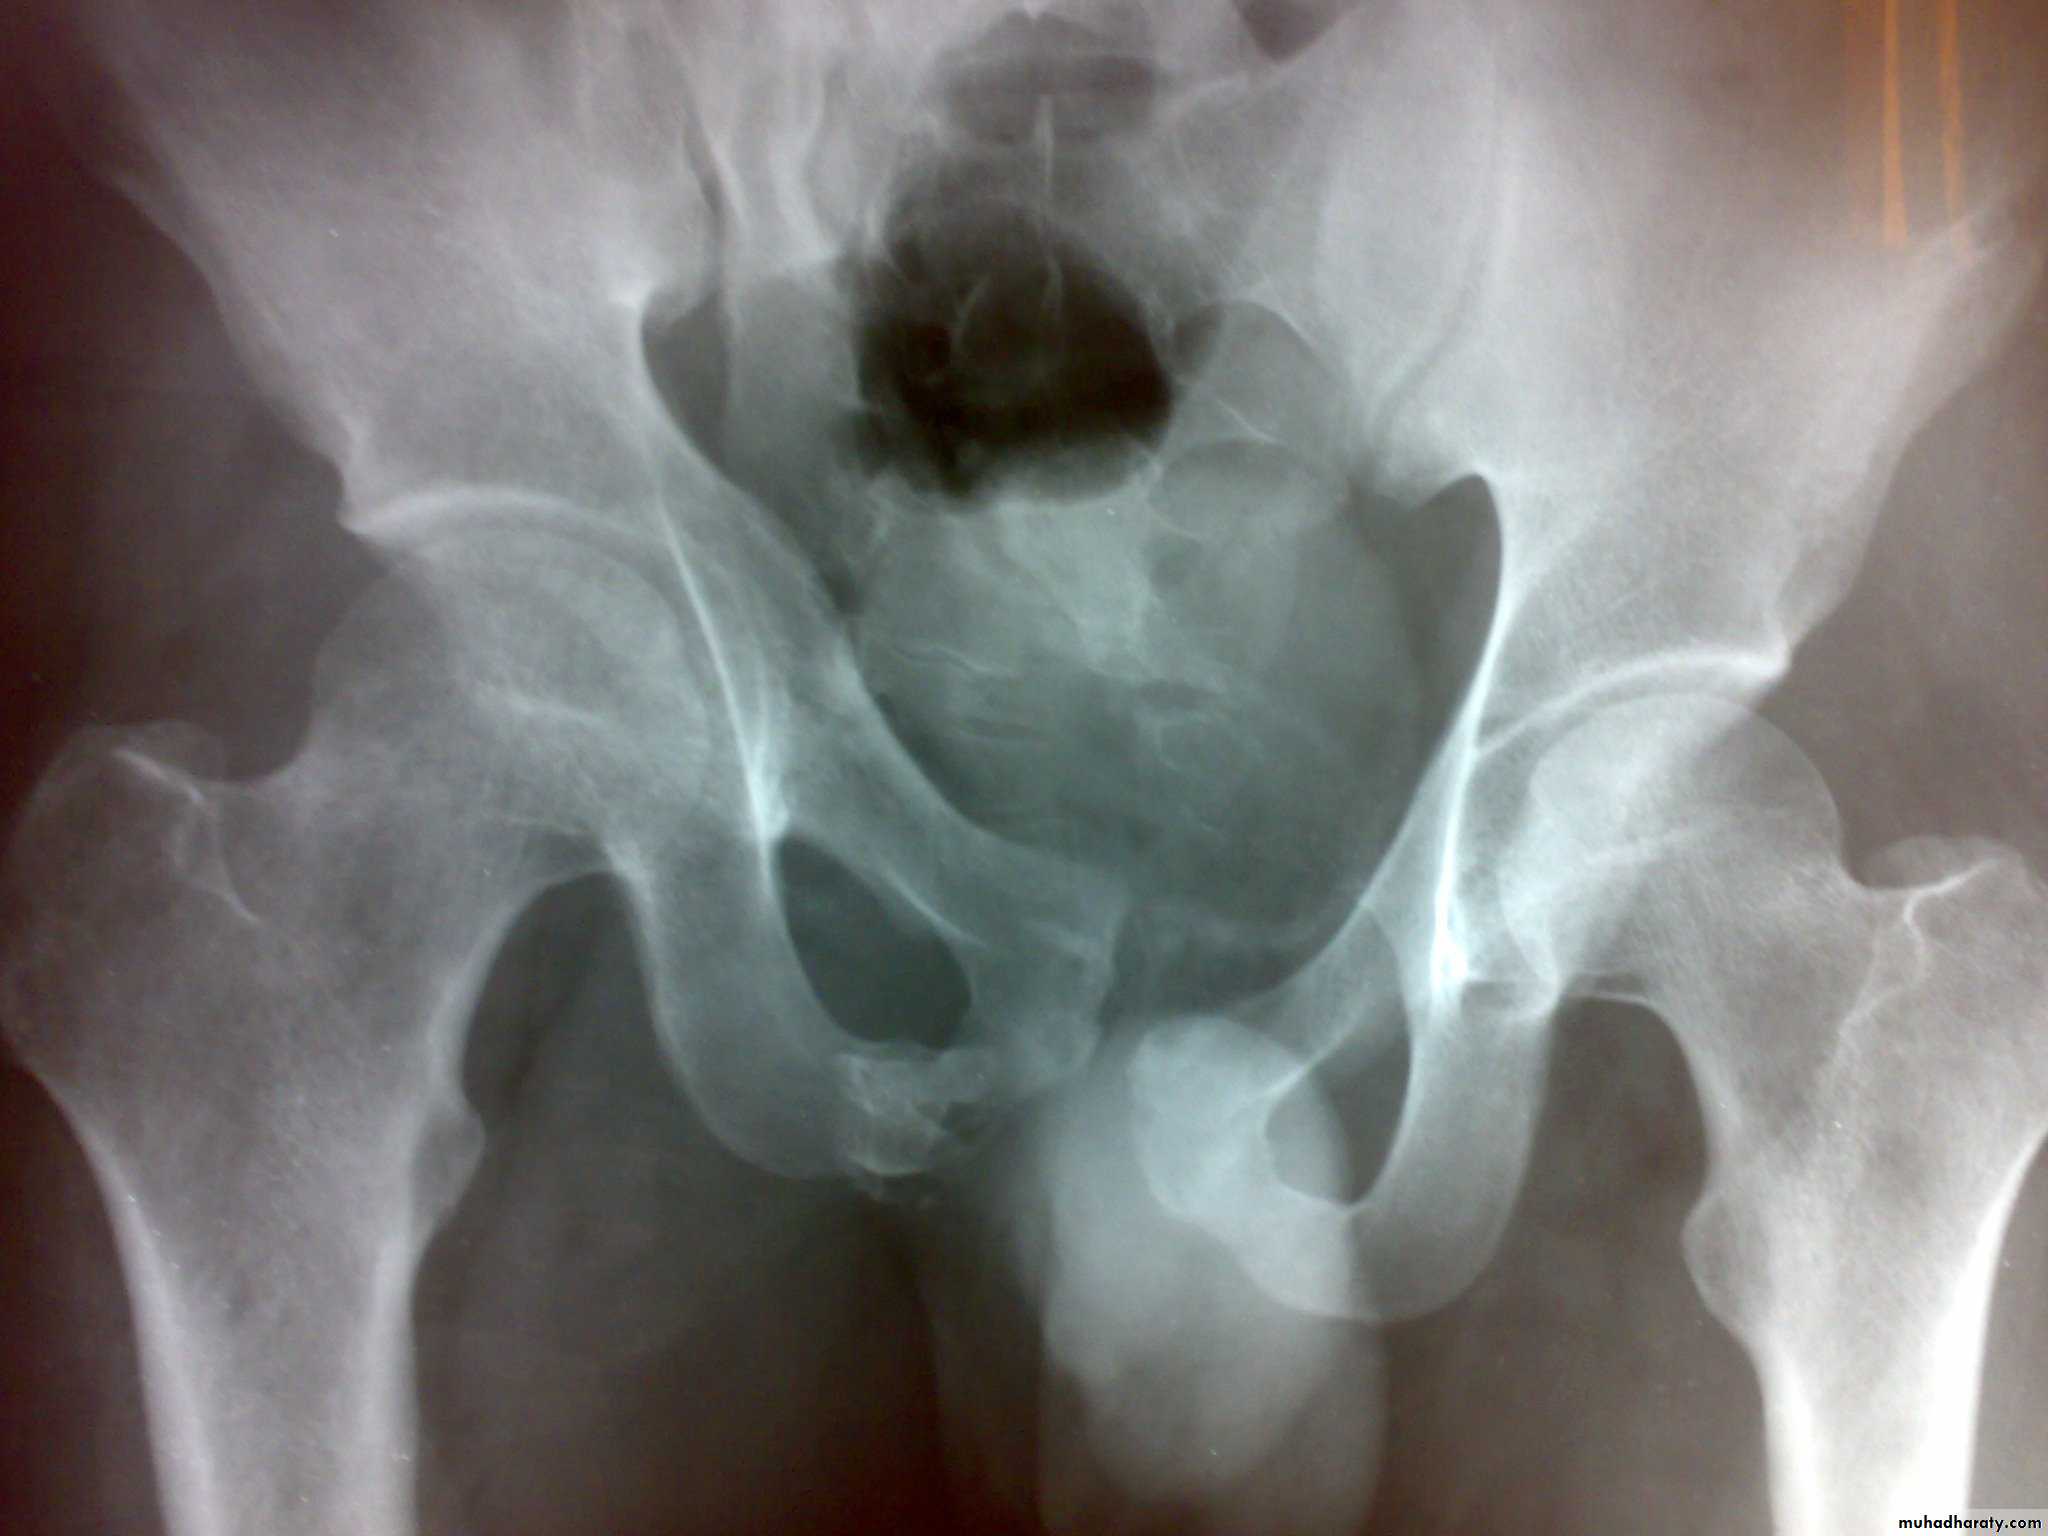

Unstable ring fractures

Caused by sever trauma.

Extremely serious.

Carries high risk of visceral injuries.

There are fractures around or separation of symphysis pubis or sacroiliac joint.

Clinically : These injuries caused by severe trauma, extremely serious, carries high risk of visceral injuries. There are fractures around or separation of symphysis pubis or sacroiliac joint. With unstable injuries, the patient is

a) severely shocked.

b) in great pain.

c) unable to stand.

d) Patient may be unable to pass urine(blood at external meatus).